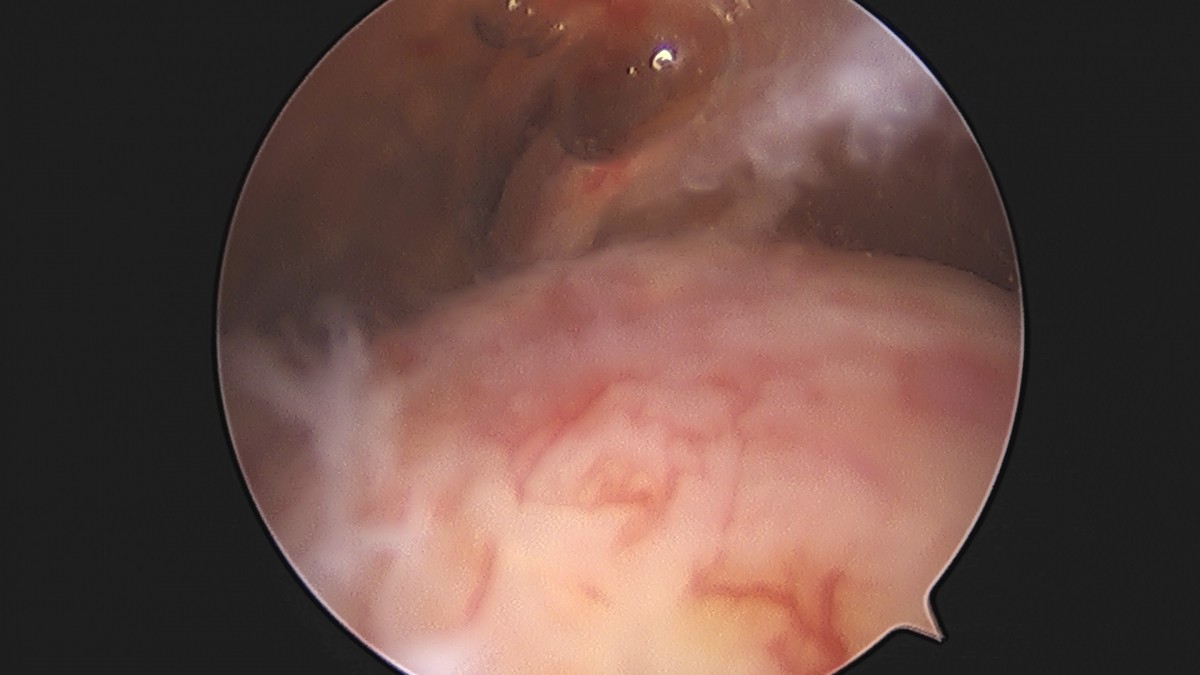

이재상원장님 어깨 석회 제거술 조광O 환자

dae765e4d9ac96aee867c9d6292d8784_1758004692_5451.jpg